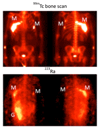

Radioisotopes of elements from all parts of the periodic table find both clinical and research applications in radionuclide molecular imaging and therapy (nuclear medicine). This article provides an overview of these applications in relation to both the radiological properties of the radionuclides and the chemical properties of the elements, indicating past successes, current applications and future opportunities and challenges for inorganic chemistry.